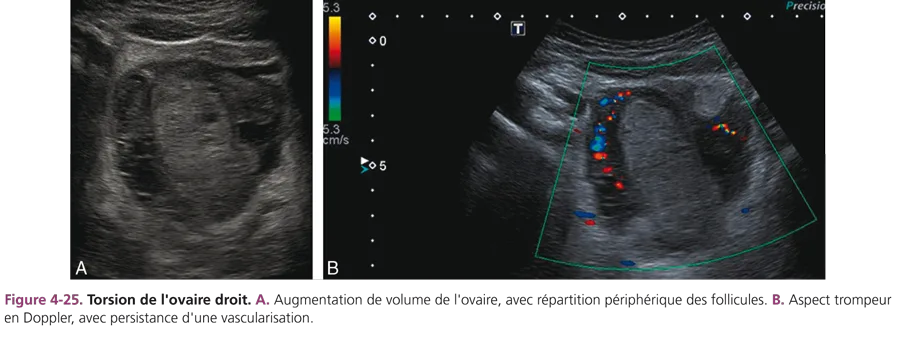

Torsion d’annexe

Il s’agit d’une rotation de l’ovaire sur son pédicule vasculaire, dont l’aspect morphologique est variable depuis l’oedème ovarien jusqu’à la nécrose. C’est une urgence chirurgicale. La torsion d’annexe peut être favorisée par un kyste ou une tumeur ovarienne. La présentation clinique classique associe une douleur pelvienne aiguë avec des nausées et/ou des vomissements. Du fait de l’hyperthermie modérée possible et d’une hyperleucocytose, à droite, la torsion d’annexe peut réaliser un tableau pseudoappendiculaire. Les formes subaiguës peuvent faire croire à tort à une tumeur. En échographie, la torsion est marquée par une augmentation de volume de l’ovaire, un épanchement dans le cul-de-sac de Douglas et un élargissement de la trompe (fig. 4-25). La présence de petits kystes centimétriques, localisés en périphérie de la masse, est un critère diagnostique majeur, mais l’aspect est souvent non spécifique, hétérogène avec contingent solide et kystique.

La présence d’un signal Doppler artériel au sein de la masse n’exclut pas le diagnostic. L’IRM a un intérêt en cas de difficulté diagnostique et de formes subaiguës, en montrant les formations kystiques périphériques et l’absence de rehaussement après injection de produit de contraste.